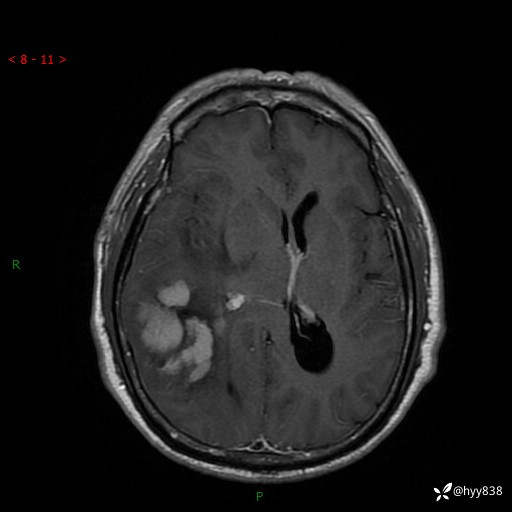

患者性别:男

患者年龄:56岁

简要病史:外院CT提示脑膜瘤,为进一步诊治来我院

临床诊断:颅脑占位

颅脑MRI平扫+增强